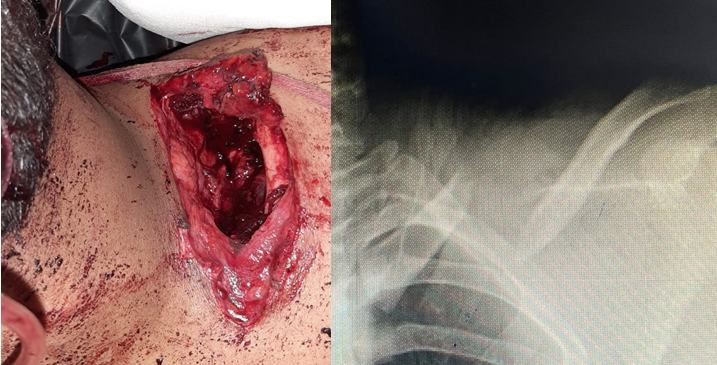

A 25-year-old male patient presented to the trauma care center of Bangalore medical college and research institute after sustaining a fall from two wheeler injuring his left shoulder. On primary survey, vitals were stable and a left Type III B open midshaft clavicle fracture (Gustilo–Anderson Classification) was noted. There was a 12 × 6 cm open wound with fractured clavicle ends exposed and gross contamination with organic matter. Deltoid and pectoralis major laceration was noted at the clavicle insertion site. No neurovascular injury was found. A wound swab was taken and sent for culture and sensitivity. Thorough wound wash was given with saline, hydrogen peroxide, and betadine. Foreign bodies were removed and intravenous antibiotics were administered as per institutional protocol. On radiographic evaluation, left midshaft clavicle fracture was revealed (Allman group 1) (Fig. 1).

Figure 1: 12 × 6 cm open wound and midshaft clavicle fracture.